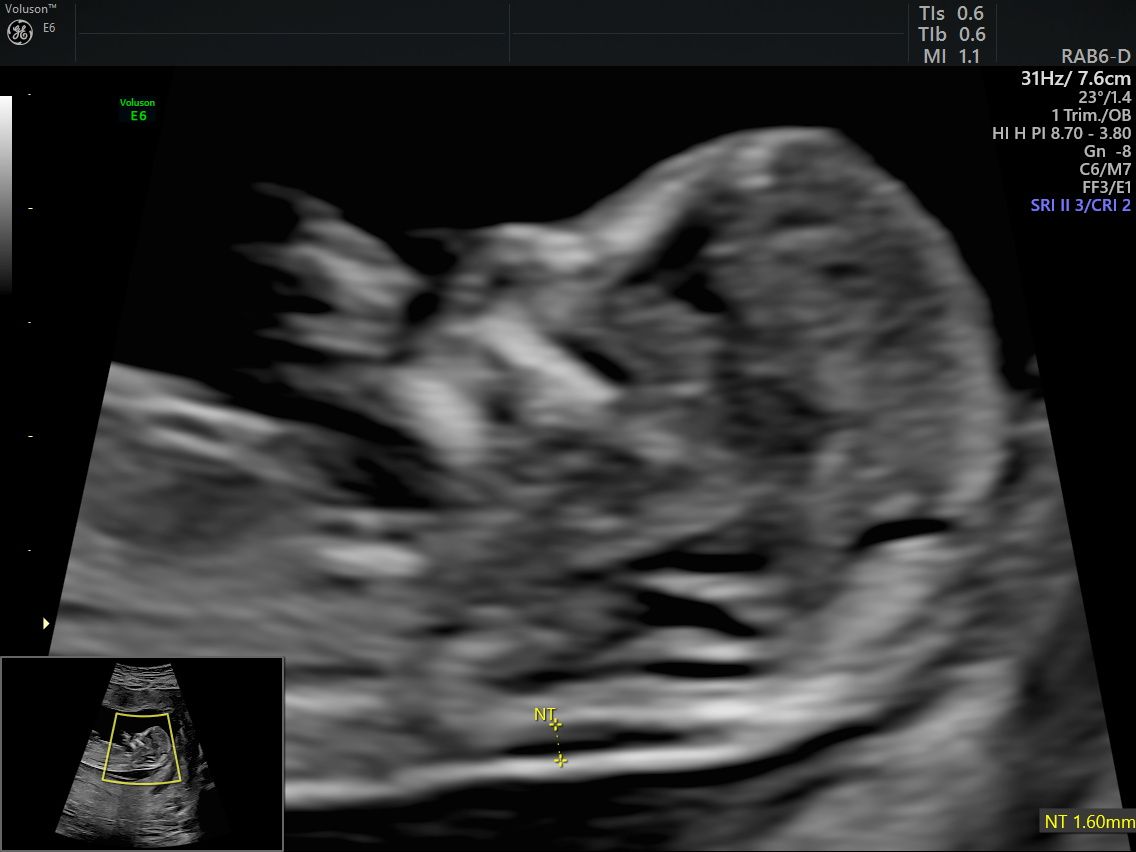

Realizo estudios con tecnología avanzada para detectar posibles complicaciones durante el embarazo. Entre ellos se incluyen ultrasonidos de tamizaje en el primer trimestre, ultrasonidos estructurales, seguimiento de embarazos gemelares y pruebas genéticas como ADN fetal, biopsia de vellosidades coriales y amniocentesis, que ayudan a evaluar la salud del bebé y del embarazo.